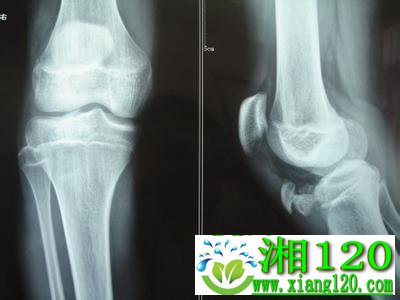

药物治疗骨折分三期治 止疼药无益于骨折恢复

治疗骨折的方法很多,有西医治疗骨折的方法,也有中医治疗骨折的方法。其中中医的针灸主要用于治疗闭合性骨折,中医还有药物治疗骨折的方法。中医药物治疗骨折一般分三期来治疗。